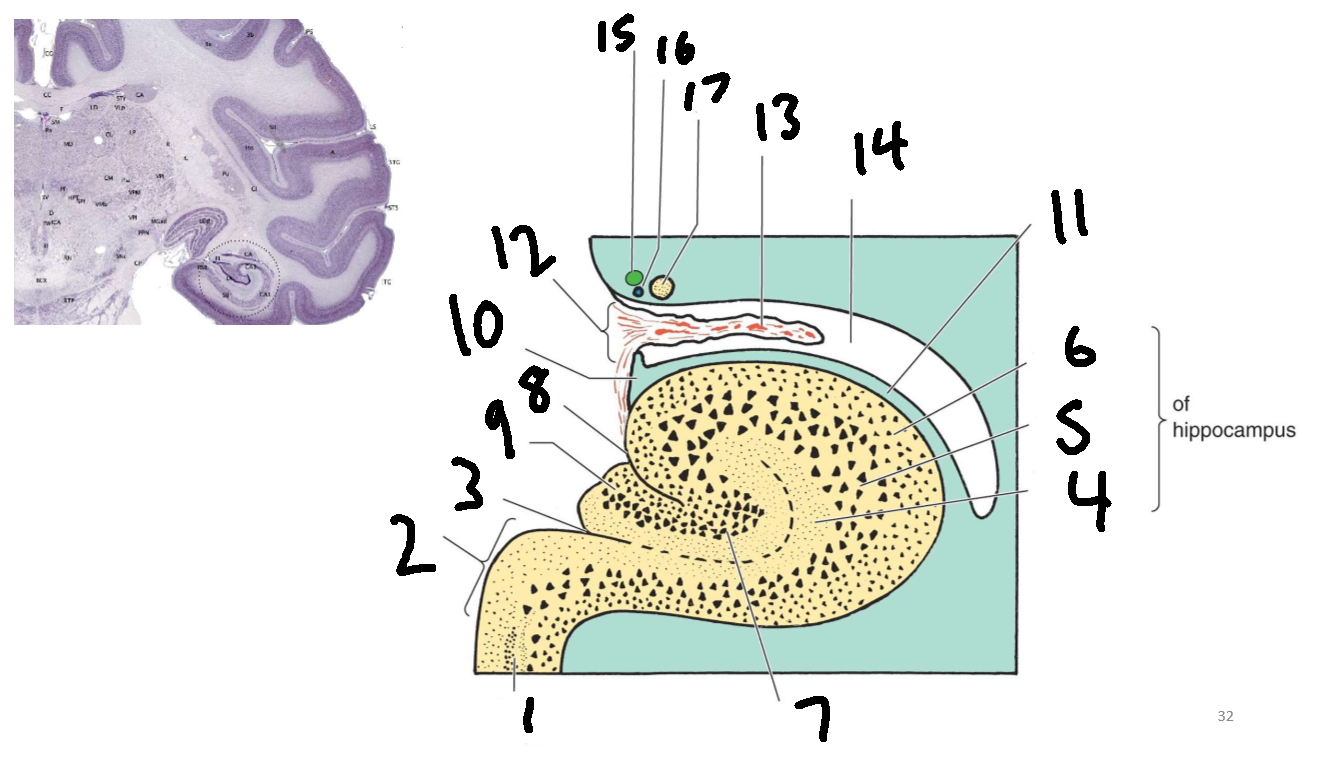

What structure is this?

hippocampus

What is 1?

hippocampus

What is 2?

rhinal sulcus

What is 3?

lateral ventricle

What is 4?

thalamus

What is 5?

entorhinal cortex

What is 6?

perirhinal cortex

What is 7?

parahippocampal cortex

What is 1?

gyrus dentatus

What is 2?

cornu ammonis

What is 3?

fimbria

What is 3’?

alveus

What is the arrow pointing to?

happicampal sulcus

What is ca1, ca2, ca3 and ca4?

fields of cornu ammonis

What is 4?

tela choroidea

What is 5?

stria terminalis

What is 6?

tail of caudate nucleus

What is 7?

temporal horn of lateral ventricle

What is 8?

collateral eminence

What is 9?

collateral sulcus

What is 10?

parahippocampal

What is 11?

entorhinal area

What is 12?

subiculum

What is 13?

lateral geniculate body